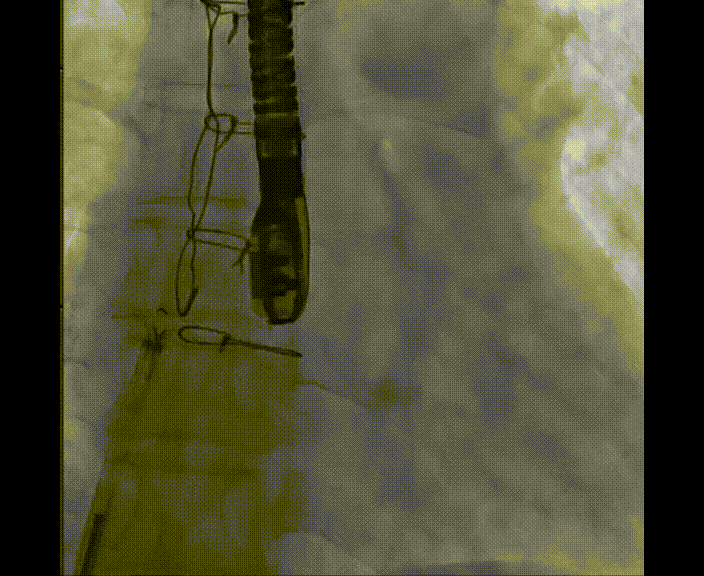

術中首先在局麻下穿刺股動脈、股靜脈,完成心導管檢查評估后轉為全麻,在食道超聲引導下穿刺房間隔,穿刺成功后將加硬導絲送入左上肺靜脈建立軌道,根據(jù)患者病情行球囊預擴張后植入6mm孔徑房間隔造孔支架,經(jīng)透視及食道超聲評估支架左右盤展開良好,夾持于房間隔兩側,固定穩(wěn)定、位置良好,食道彩超顯示房水平右向左為主分流,分流孔直徑符合預期大小,心導管檢查評估達到預期效果,釋放造孔支架。術后12h患者下床活動,恢復順利,擬于近日完善術后評估后出院。